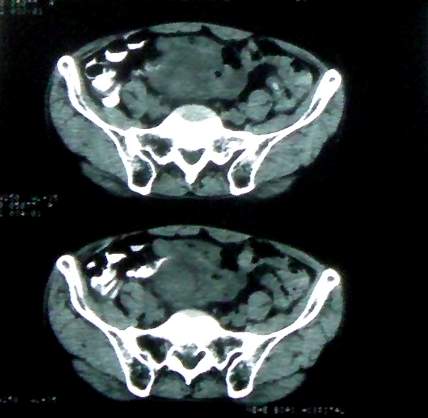

男 60岁,下腹部肿块半年余

前列腺肥大,密度不均。伴盆腔实性肿块。考虑前列腺癌伴盆腔转移。建议增强扫描。

盆腔恶性占位,间质瘤可能性大

乙状结肠间质瘤

病理结果:肠系膜肉瘤

病灶形态不规则,偏心性裂隙样坏死,支持恶性病变。来源不好定。感谢反馈结果--肠系膜肉瘤。